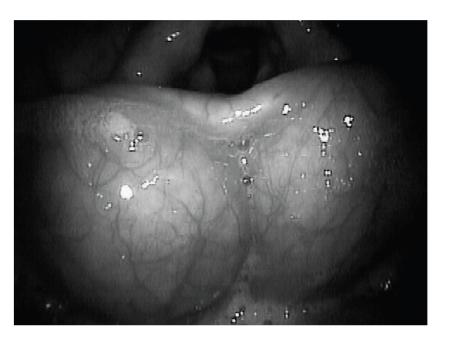

Cysts of the vallecula are rare, accounting for 10.5% to 20.1% of all laryngeal cysts. Vallecular cysts may present with diverse symptoms affecting the voice, airway, and swallowing. We describe the evaluation and treatment of a 70-year-old woman who presented with dysphagia caused by large bilateral vallecular cysts.

会厌谷囊肿罕见,占所有喉囊肿的10.5%至20.1%。会厌谷囊肿可能表现出影响声音、气道和吞咽的多种症状。我们描述了一名70岁女性因双侧巨大会厌谷囊肿导致吞咽困难的评估和治疗情况。